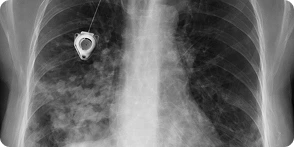

A PowerPort functions as an implantable venous access device. The device receives placement through skin tissue which doctors typically insert into the upper chest area while connecting it to a thin catheter that enters a big vein. The medical staff can use a particular needle for blood draws and medication administration after the device receives its implantation.

The medical evidence needs proof of implantation which can be found in operative reports and device records that show the exact date of implantation.

The report needs to include imaging and diagnostic reports which show the catheter position or breakage through X-ray and CT scans.